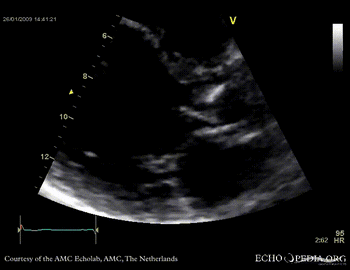

Aortic valve endocarditis with vegetation

Case description: This patient had endocarditis with an aortic valve vegetation

PLAX showing an aortic valve vegetation PLAX Excentric aortic valve regurgitation